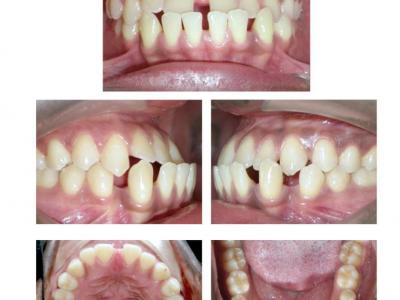

Les deux patients sont classe III squelettique (léger) avec un articulé inversé antérieur, mais avec des rapports de classe I molaire et des diastèmes.

Des dispositifs multi-attaches linguaux ont été choisis pour des raisons esthétiques et pour avoir des torques individualisés.

La principale astuce a été de placer des mini-vis vestibulaires (impossibles en lingual à cause de l'inconfort et de la perte de celles-ci avec les contraintes linguales), de tendre une chaînette entre ces mini-vis en vestibulaire et de bloquer l'élément élastomérique par un point de composite sur les incisives centrales inférieures. L'intérêt est de ne pas avoir recours à des élastiques inter-arcades et donc de ne pas compenser le haut (version inesthétique des incisives supérieures), de ne pas basculer les plans d'occlusion et de ne pas solliciter la coopération des patients. Ceci nous a aussi dispensé de chaînettes linguales, sources d'accumulation bactérienne.

Le recul des incisives inférieures a permis la correction de l'articulé inversé et repositionné les lèvres (gain esthétique). Les torques ont été bien contrôlés avec des systèmes différents (le premier avec une insertion verticale de l'arc au niveau antérieur et le deuxième avec une insertion horizontale). Le contrôle du torque ne dépend donc pas du type d'insertion, mais du niveau d'insertion de l'arc dans les attaches (insertion au fond pour contrôler) et du jeu de l'arc dans ces dernières.

Dans le deuxième cas, une autre astuce a été de placer des cales indentées sur les molaires pour ouvrir l'occlusion (et donc permettre le passage des incisives inférieures derrières les supérieures), tout en gardant des rapports de classe I latéraux grâce aux indentations (renfort d'ancrage).